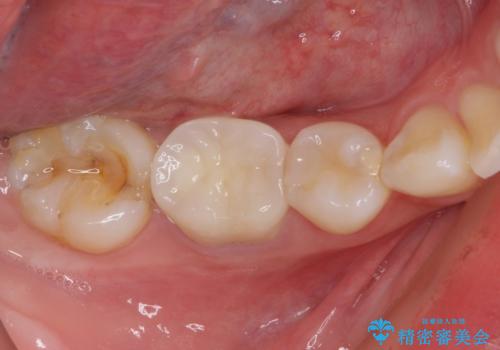

前医での根管治療の度に感じていた痛みの原因は分かりませんでしたが、元々違和感すらなかった歯であったので、速やかに根管治療を行った後に、ジルコニアクラウンを装着しました。

咬み合わせが強く、歯の高さが非常に低かったため、審美性には劣るものの、高強度であるフルジルコニアクラウンを採用しました。